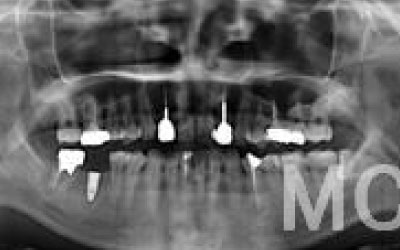

ブリッジとインプラントでは、前後の歯の寿命に大きな違いがあります。ブリッジでは、支えとなる歯を虫歯がなくても大きく削る必要があり、さらに噛む力が通常の1.5倍かかるため、その寿命が短くなりがちです。実際の統計によると、ブリッジの支えとなる歯の68%が、10年以内に抜歯を余儀なくされるという結果が出ています。

噛むとき、誰でも歯に何十キロもの力がかかっています。当然、歯の本数が減れば減るほど、残った歯にかかる負担は大きくなります。ブリッジ治療の場合、失われた歯にかかっていた力は、前後の歯で支えることになります。その結果、残った歯には、抜歯していないときに比べて1.5〜2倍程度の力がかかることになります。

ブリッジなどの治療では、前後の歯を大きく削る必要があります。場合によっては、虫歯がないのに歯の神経を取らなければならないこともあります。実際、神経を取って被せ物をすると、その歯は一気に「最終段階」に進んでしまうのです。しかし、インプラント治療では、前後の歯を削ることも、神経を取ることもありません。歯の寿命を延ばすためにも、健康な歯をできるだけ削らないことが非常に重要なのです。

ブリッジの支えの歯は、データでは10年以内に68%が抜歯になります。